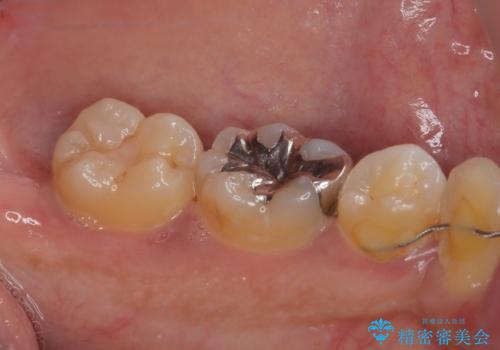

- セラミックにやり替えたいとのことで来院された患者様です。検査の結果、レントゲン上でメタルインレーの不適合を認めたのでセラミックインレーによる修復治療を行っていくことにしました。

拡大鏡視野下で、メタルインレー、虫歯の除去を行い、セラミックインレーに適した形に整えました。